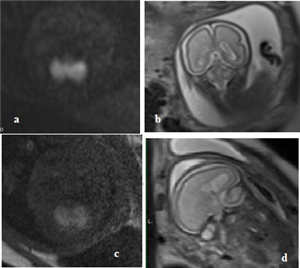

Hội chứng Joubert: Báo cáo ca và hồi cứu y văn